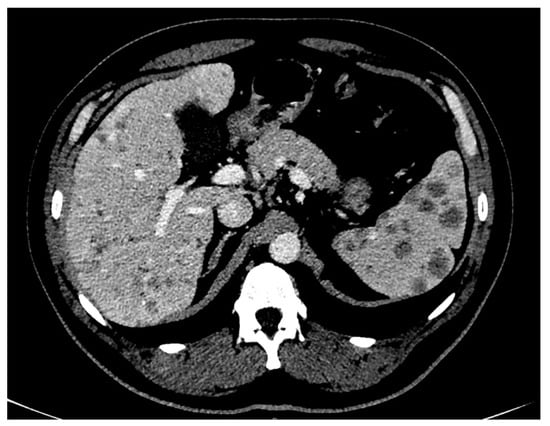

2. Case Presentation